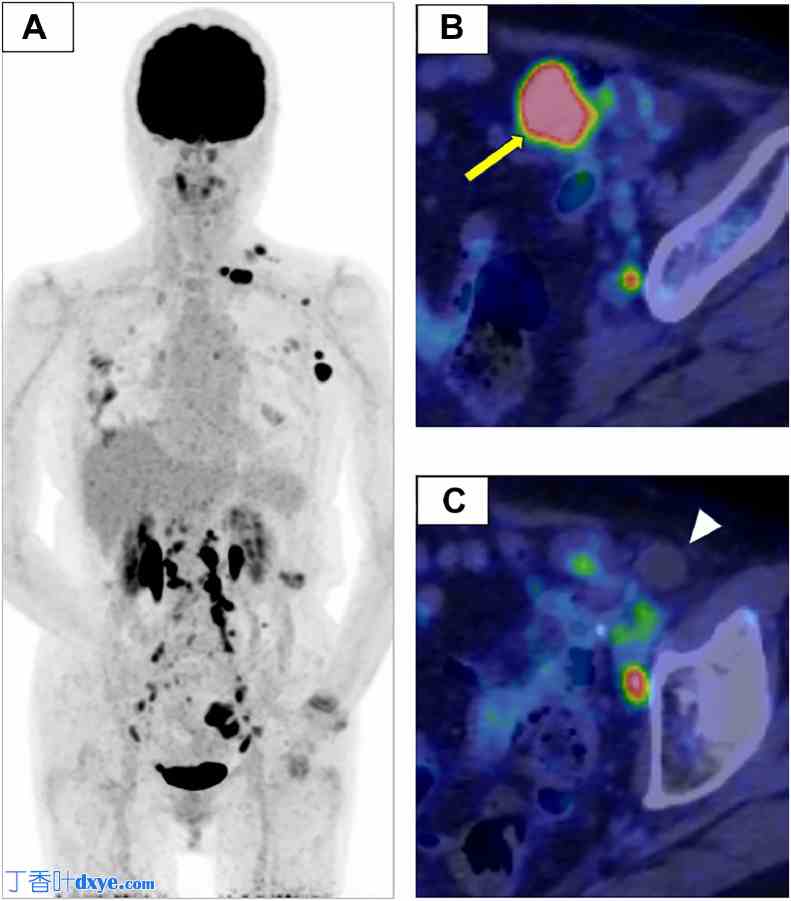

氟脱氧葡萄糖正电子发射断层扫描/计算机断层扫描 (FDG-PET/CT):最后,FDG-PET/CT(图 3)显示左下腹部实性部分存在 FDG 摄取,最大标准化摄取值为 10.8。PET 显示左锁骨上、腋窝、主动脉旁和盆腔区域多个肿大淋巴结存在 FDG 摄取,表明淋巴结转移。根据淋巴结活检和影像学检查结果,怀疑是多发性转移的 FTC。

图 3。

正电子发射断层扫描-计算机断层扫描 (PET/CT)。(A) 最大强度投影 (MIP) 图像、(B) PET-CT 融合图像(实体肿瘤水平)和 (C) PET-CT 融合图像(腹股沟疝水平)。左侧 MIP 图像 (A) 显示左锁骨上窝、腋窝、主动脉旁区域和骨盆中多个肿大淋巴结,FDG 摄取,显示淋巴结转移。左下腹部实体部分 (B,箭头) 显示相应的 FDG 摄取(SUV 最大值为 10.8)。在 MRI 上观察到的高水含量香肠形结构中可见最小 FDG 摄取 (C,箭头)。香肠形形态是扩张输卵管的特征。病变内的实体成分表现出高代谢活动和强烈摄取,而液体或分泌成分则表现出弱摄取。双肺可见FDG摄取浸润影,提示非结核分枝杆菌病加重。